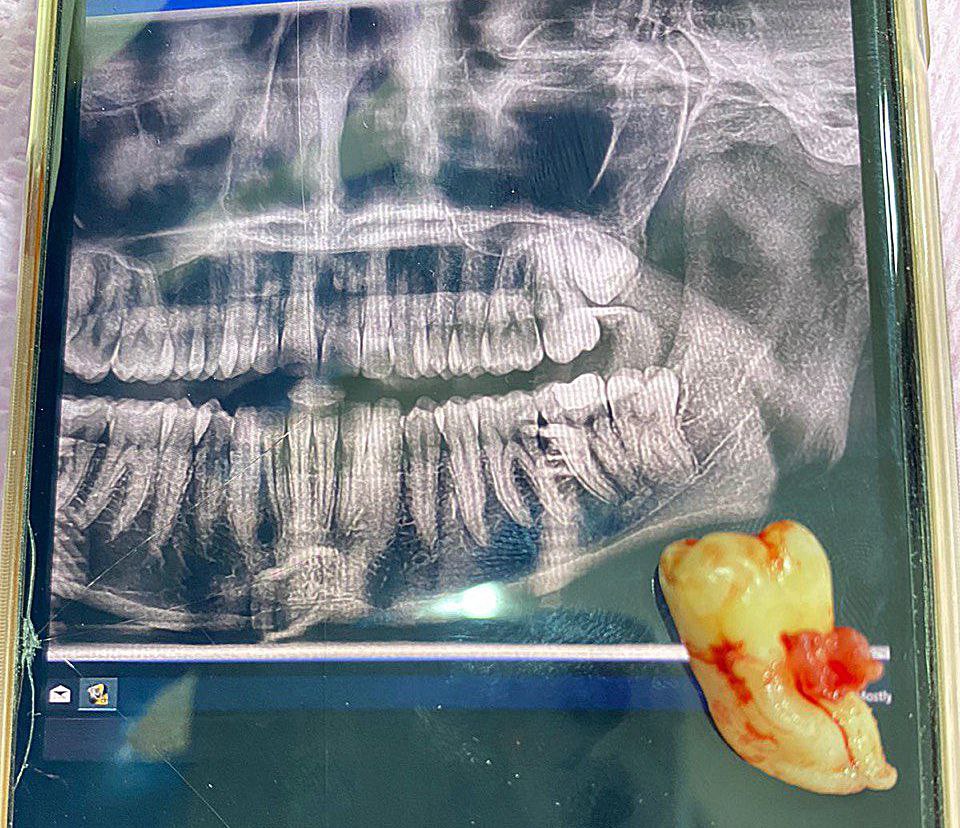

أجراء عملية قلع سن العقل لمريض في عيادة جراحة الفم

9 Nov

2022/11/09 اقرأ المزيد